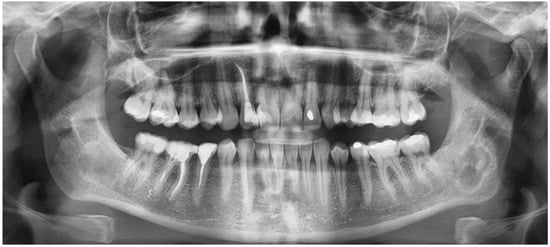

- mixed radiolucent/radiopaque lesion (depending on the stage of COD maturation), Figure 1.

- present in the jaw/maxilla in tooth-bearing areas, Figure 3

- radiolucent with/without radio-opacities with thin radiolucent rim, Figure 2

- self-limiting radiolucency, Figure 4

- associated with anterior/posterior teeth (Figure 2)

- various stages of calcifying masses inside of the lesion, Figure 5

- may cause cortical expansion or teeth displacement, Figure 5.

- no changes within the teeth root apex, Figure 3